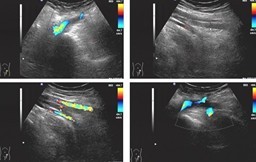

2009年1月6日(即术后27天),患者因“左全髋关节置换术后左小腿肿胀一周,进行性加重”入院。入院体检:左膝关节以下重度肿胀,皮肤发亮,皮温稍 高,轻压痛,左足部感觉、运动、血运可。1月7日行左下肢动静脉彩超示:左侧胫后静脉近心端内异常实质性回声,考虑深静脉血栓形成,双侧胫前静脉显示不 清。凝血五项示:APTT:22.7 (正常24.5—36.0),D-二聚体1667 μg/L (正常0—324μg/L)。诊断为左小腿深静脉血栓。予以速碧林,低分子右旋糖苷等药物抗凝,对症支持,患者左小腿肿胀部分缓解。09年1月14日复查 左下肢动静脉彩超示左侧股静脉,腘静脉及胫后静脉近心端内异常实质性回声,考虑深静脉血栓形成。同日复查凝血五项示:APTT:24.3(正常24.5— 36.0),D-二聚体546 μg/L (正常0—324μg/L)。考虑患者左下肢血管栓塞范围较广,请血管外科会诊后转入血管外科继续进一步治疗。转入血管外科后,予病人速碧林抗凝,尿激酶 溶栓,同时对症支持治疗。1月16日复查左下肢血管彩超示:左侧腘静脉内异常实质性回声,考虑深静脉血栓形成不完全阻塞。1月22日复查凝血五项 示:APTT:24.1(正常24.5—36.0),D-二聚体204 μg/L (正常0—324μg/L)。患者左下肢肿胀明显减轻,胫前仍有轻微水肿,生命征稳定,无诉其他不适。考虑患者病情明显好转,予以出院,嘱其院外继续抗凝 治疗,定期复查凝血功能,不适随诊。

彩色多普勒是检查下肢深静脉血栓形成的无创方法,可反复检查,诊断率可达 90%。血栓形成时主要表现为深静脉管腔扩张、管腔内充满大量低弱回声物,无血流通过征象,治疗好转者表现为深静脉管腔变窄,管腔内低弱回声物减少,有血 流通过征象。静脉造影敏感性和特异性均较高,但其为有创检查。阳性结果主要为静脉内出现恒定的缺损、正常充盈的静脉突然中断、静脉主干不显影等。一般主张 对下肢手术后出现小腿疼痛患者立即行影像学检查,首选彩色多普勒检查。而彩色多普勒在本例患者的诊断,判断治疗效果方面也呈现重要作用。